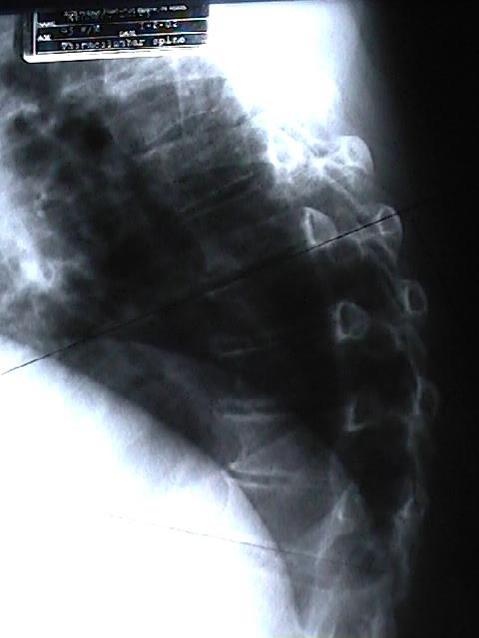

Well, the spine’s uprightness allows us humans to wander around our Juneau worlds with ease: eyes forward, head up, feet one step in front of the other. The gentle curves balance us well. Normal. This normal state is how most Juneau folks exist thankfully. On the other hand, a few Juneau people find themselves with back pain conditions that are not normal and actually cause pain. One such condition is ankylosing spondylitis (AS), a condition Aurora Chiropractic Center finds to be quite responsive to Juneau chiropractic care. But first, more about AS and the latest findings.

Now, medical literature points out that AS patients have a 5-fold higher risk of clinical spine fracture and a 35% increased risk of non-vertebral fracture. This extra risk peaks early, in the first 2 and a half years of AS disease. It is recommended that AS patients be assessed for fracture risk early after their AS diagnosis. (3) Trust Aurora Chiropractic Center to do this for you or your loved one with AS.